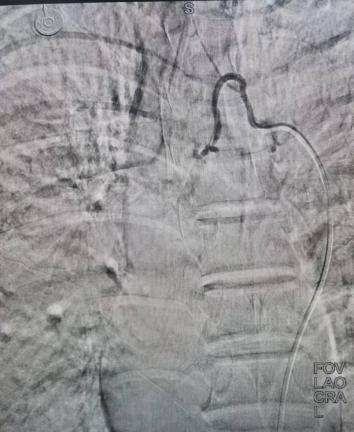

案例一:谭先生,66岁,右肺鳞癌IIIA期。2025年11月18日,在DSA引导及局麻下行经导管支气管动脉栓塞化疗术,术后肿瘤血供明显减少。

栓塞前血供丰富                                                 栓塞后血供明显减少